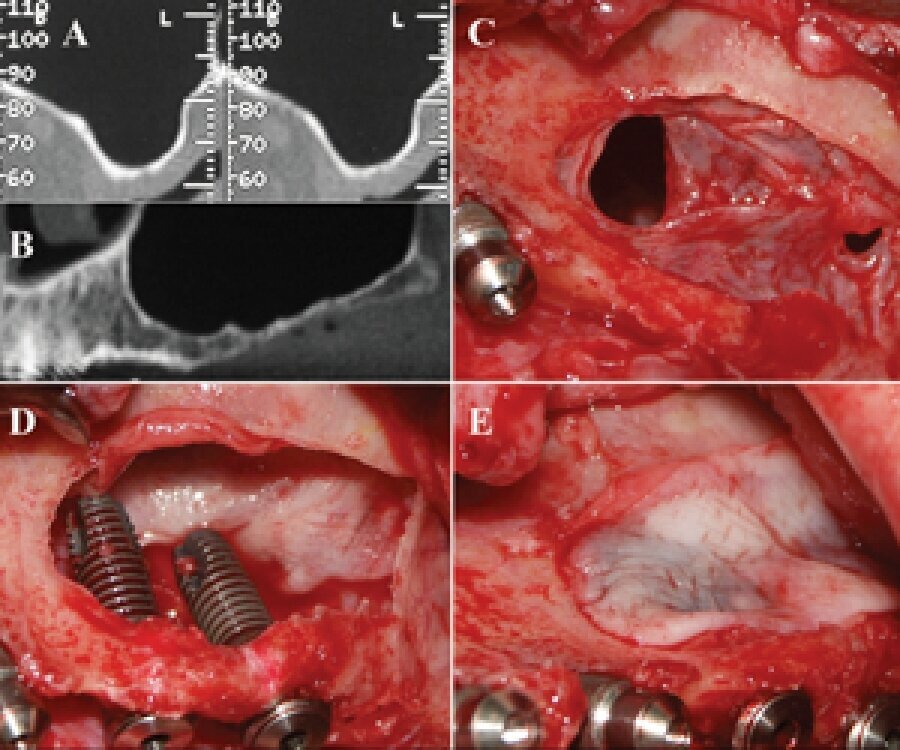

Figs. 10a-e: PRF is used in invasive surgery.

PRF is used in invasive osseous surgery close to the eyes, ear, brain and in direct contact with bone, maxillary sinus, veins, arteries and nerves that could be adversely affected, if proper contamination control protocols are not followed.